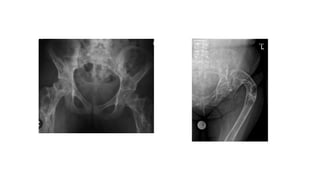

• Common sites – Ischium, ilium, sacrum and proximal femur

ENDOSTEMA • Discrete areaof sclerosis usually called a bone island • It is usually asymptomatic and incidentally found • Common sites – Ischium, ilium, sacrum and proximal femur